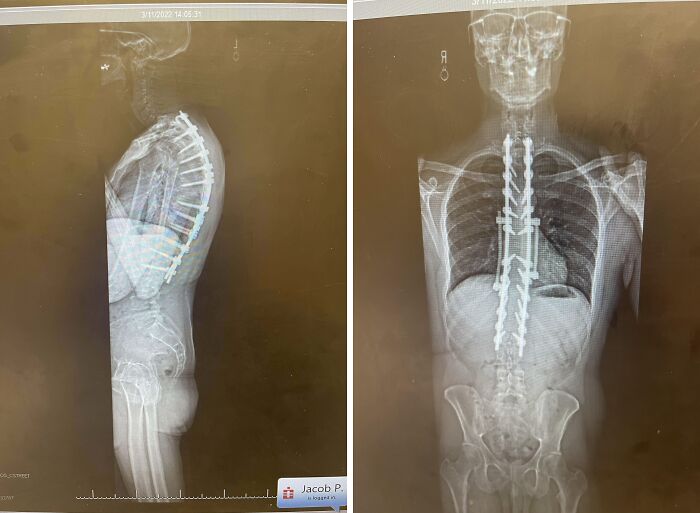

In My Head, The Screws From My Spinal Fusion Surgery Looked A Lot Smaller

Last September I Had Corrective Surgery On My Back And Now I Have 4 Rods, 22 Screws And 2 Hooks In My Body